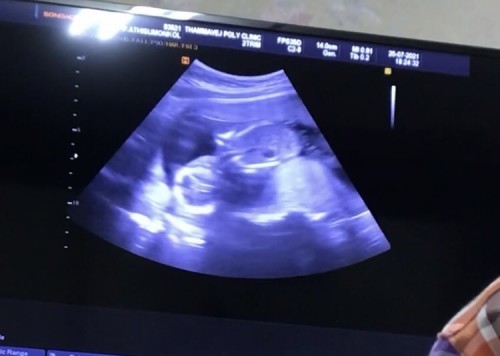

จะมาสอบถามแม่ๆที่ฉีดวัคซีน az เข็มที่ 2 แล้ว อาการเป็นไงคะ ส่วนแม่เข็มแรกตอนท้อง4 เดือน ไข้หนัก ปวดทั้งตัว ลูกหัวทิ้มตามภาพ ตอนนี้กลัวเข็มที่2 ลังเล จะไปหรือไม่ไปฉีดดี กลัวลูกจะเสียอย่างในข่าวค่ะ ขอคำแนะนำทีค่ะ